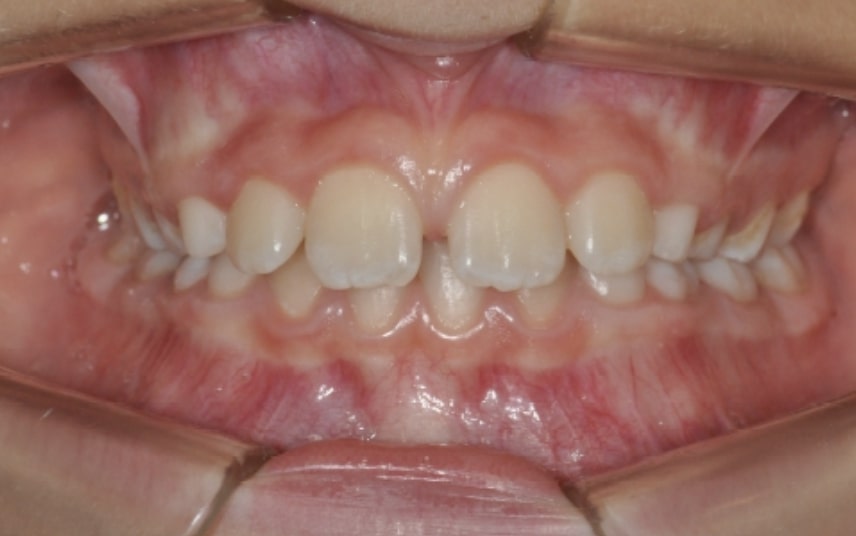

Section Class II division 1 malocclusion

Malocclusion A6 Correction of Mandibular Retrusion in Growth phase patient | Skeletal Class II | Class II Division 1 malocclusion | Deep bite | Mixed dentition

Clinical examination and diagnosis

- Molar and Canine class 2 on the right side – Molar and Canine clss 1 on the left side

- Upper diastema (11-21)

- Increased Overjet

- DeepBite

- Deviated Lower Midline 2 mm to the Right